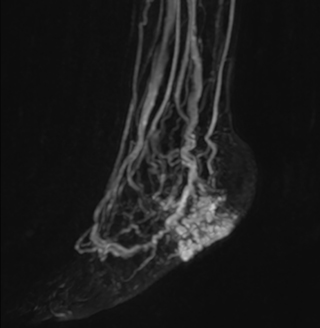

Another example is the foot examination for diabetic patients, which has improved dramatically. “The forefoot is generally difficult to image with MRI because of the inhomogeneities that the toes create – it’s hard to obtain good fat saturation in that area. Here, mDIXON made a huge difference right away, we obtain much better image quality,” Dr. Peña says. “Using mDIXON, Compressed SENSE and the dS FootAnkle coil, we have been able to reduce the scan time, so that we can now also include an additional 3D STIR sequence to visualize both arteries and veins in the foot.”

Avila adds: “In addition, since most of these patients are in a significant amount of pain, it’s important to perform the examination as quickly as possible. With Compressed SENSE and mDIXON we have been able to reduce the scan time from about 45 minutes to just 15 minutes. Not only does this improve patient comfort, we see that it also helps us acquire images without motion artifacts, which is critical to making a confident diagnosis.”